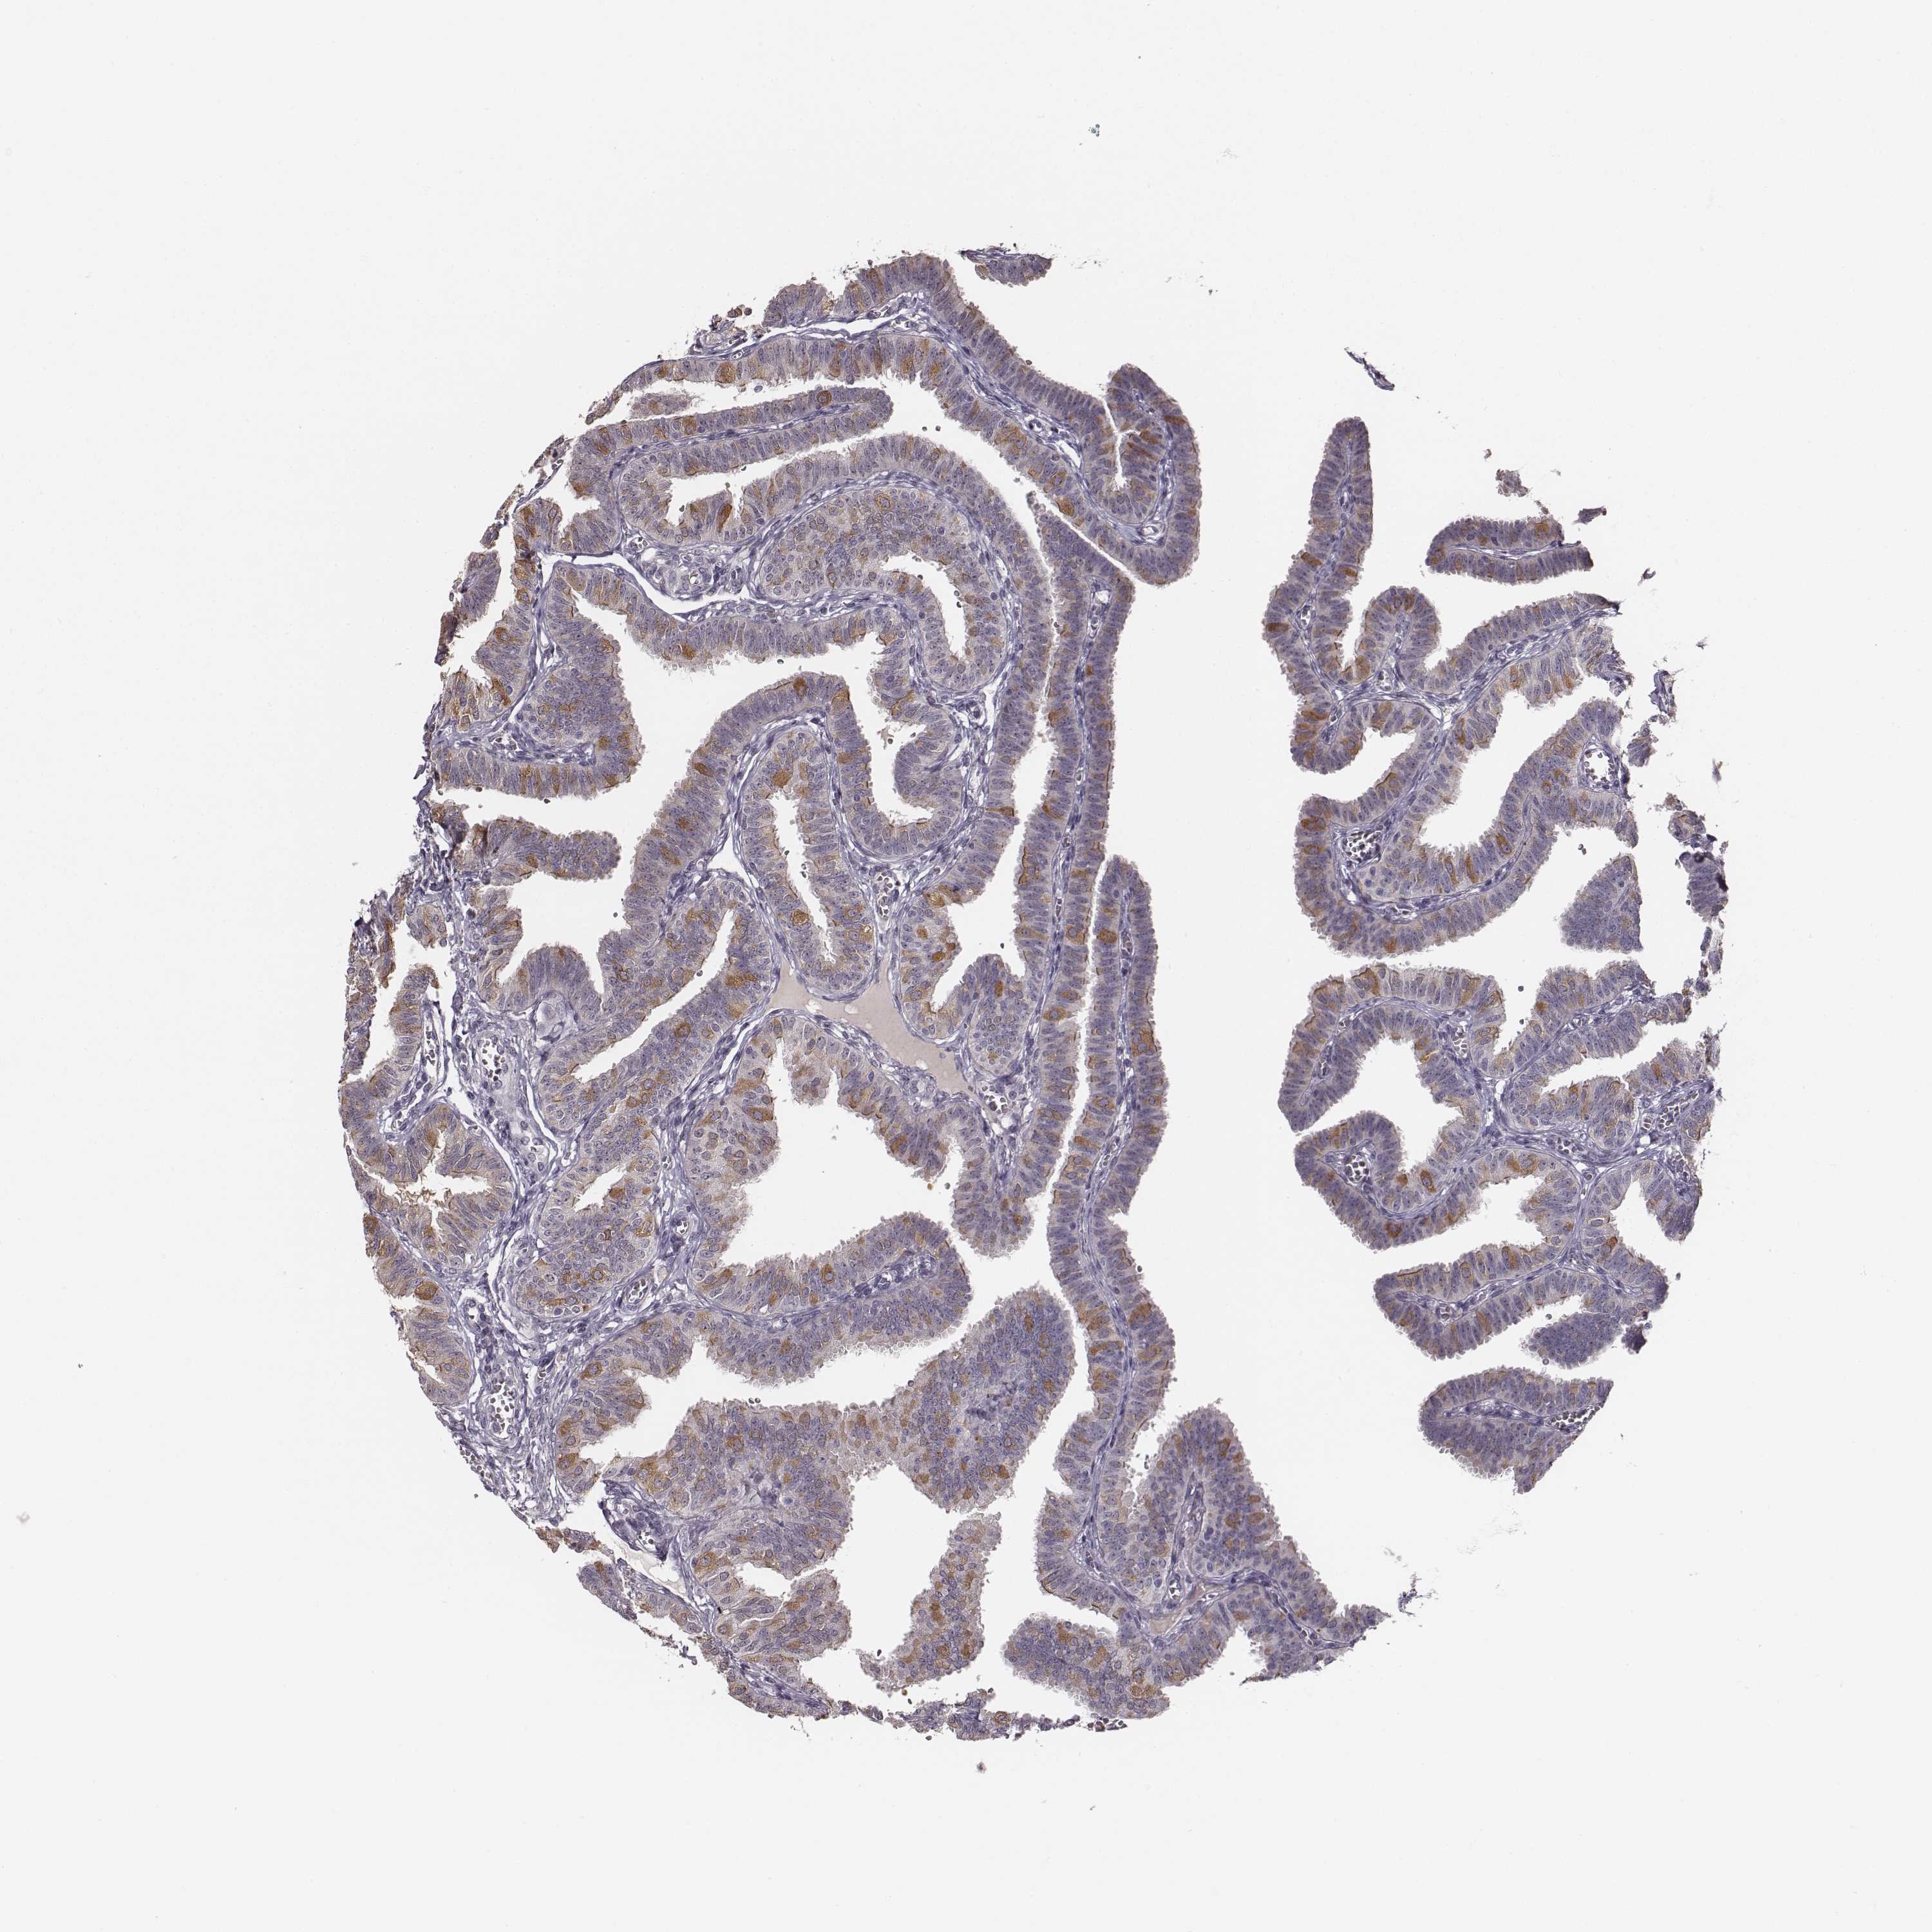

KAAG1